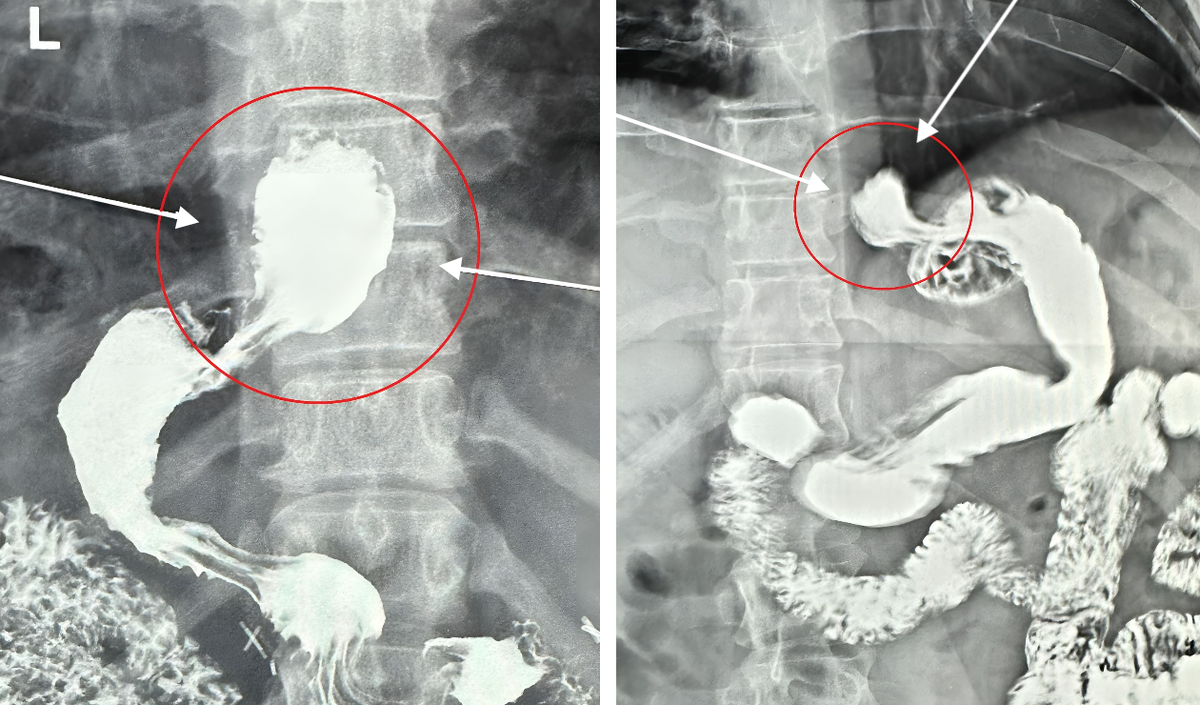

При рентгенологическом и эндоскопическом исследовании диагностируют расширение диаметра трубчатой культи желудка, признаки рефлюкс-эзофагита на фоне грыжи пищеводного отверстия диафрагмы, а также рефлюкс-гастрит – как следствие функциональной несостоятельности привратника.

Рентгенограммы культи желудка после выполнения СЛИВ. Грыжа пищеводного отверстия диафрагмы (обозначена стрелками)